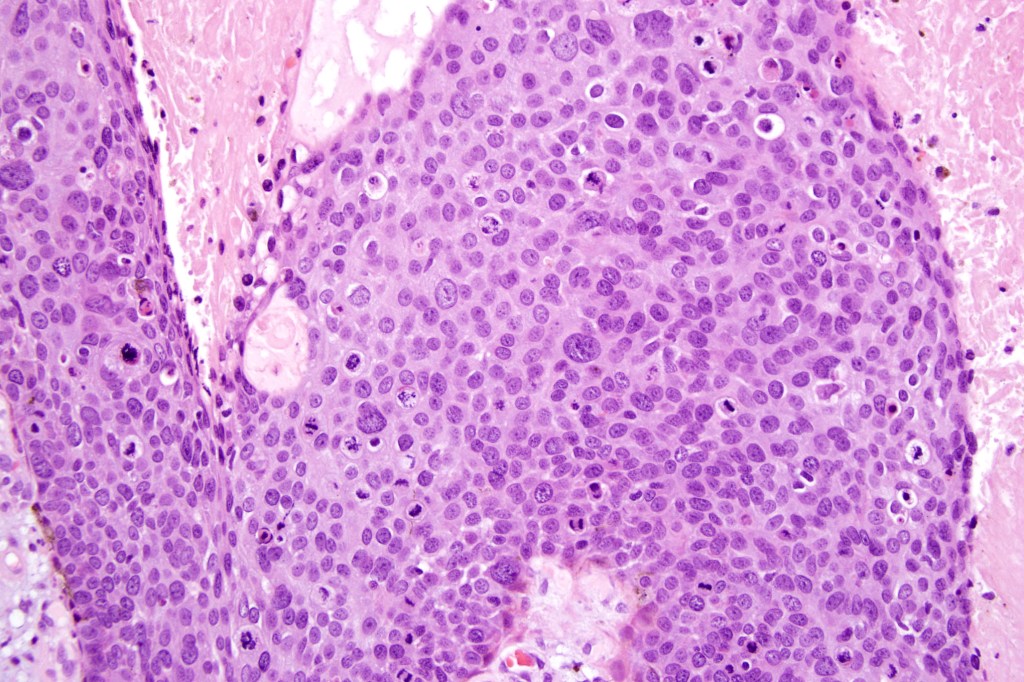

•Varying degrees of squamous differentiation- well, moderate, poorly, undifferentiated & anaplastic

•Variable pleomorphism

•Mitoses typically numerous & may be atypical